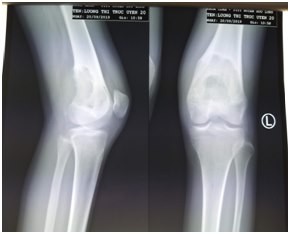

Phim chụp X-quang phần xương đùi của bệnh nhân